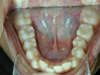

Vues avant le traitement